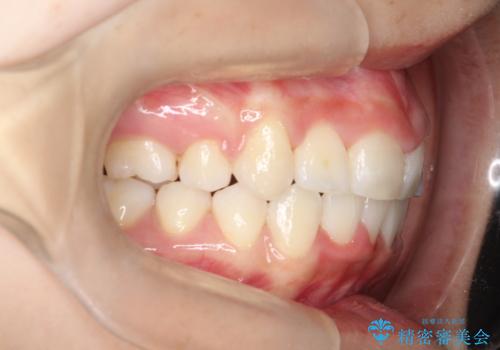

前歯のがたつき・出っ歯 ワイヤーによる抜歯矯正